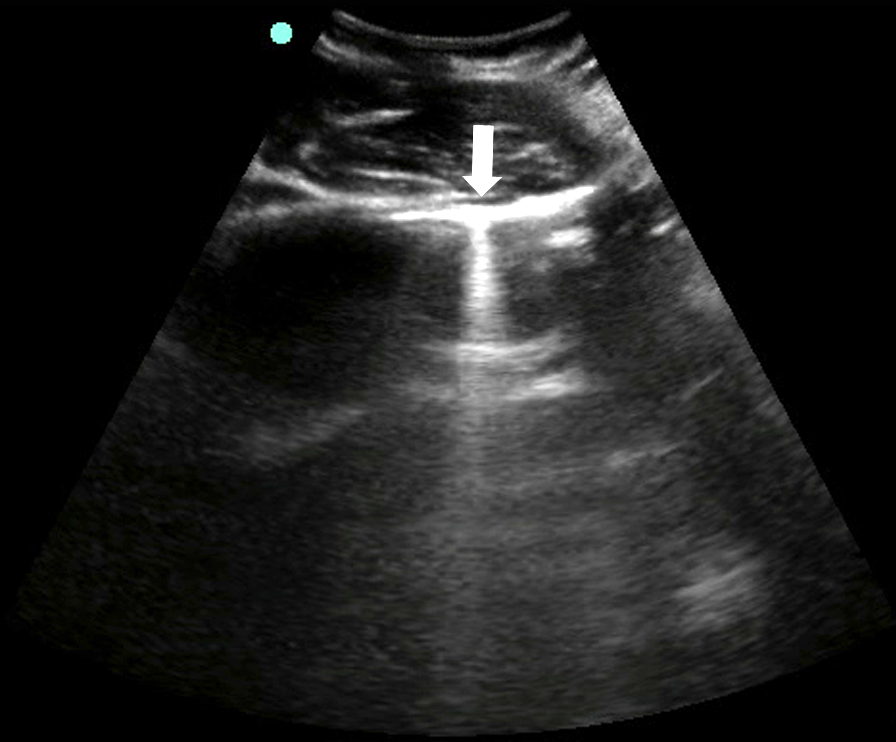

- Figure 3. Bat sign

- The closely apposed visceral and parietal pleura cannot be differentiated and appear as one hyperechoic horizontal line deep to the intercostal muscles.